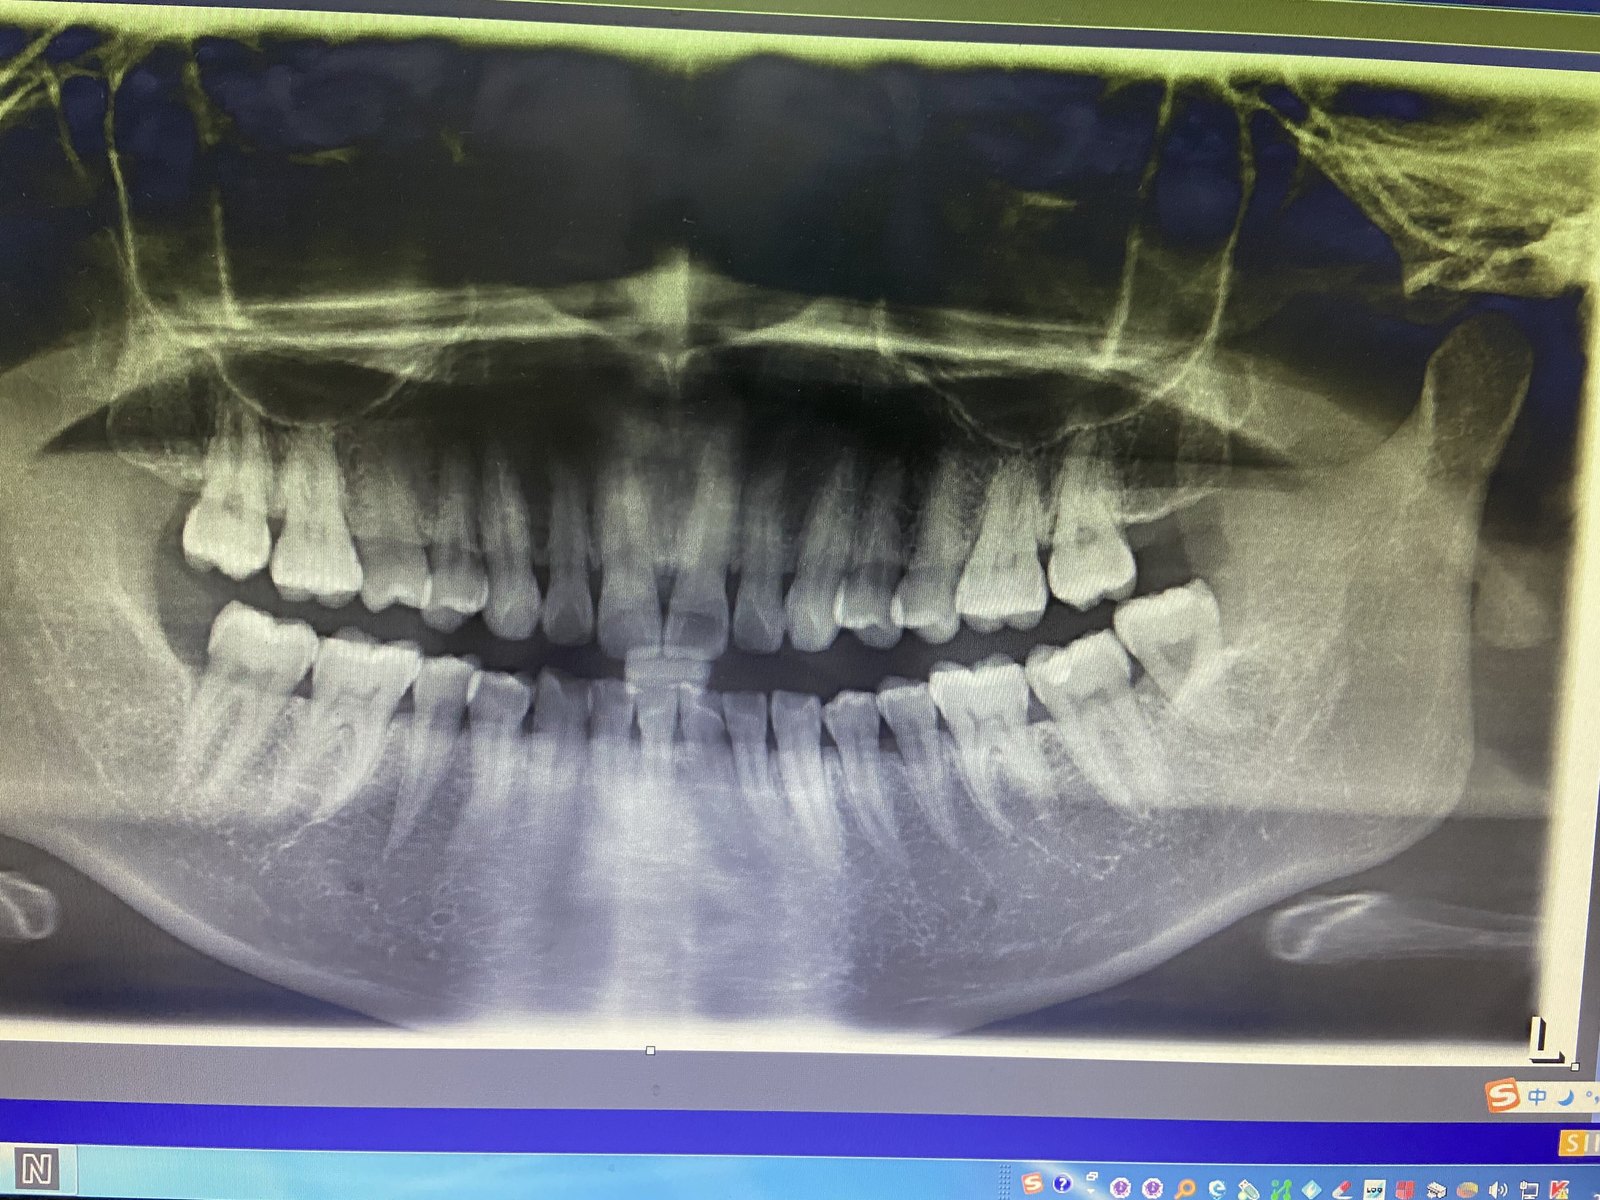

复杂智齿、牙根尖严重弯曲

左下智齿

严重时根尖段弯曲